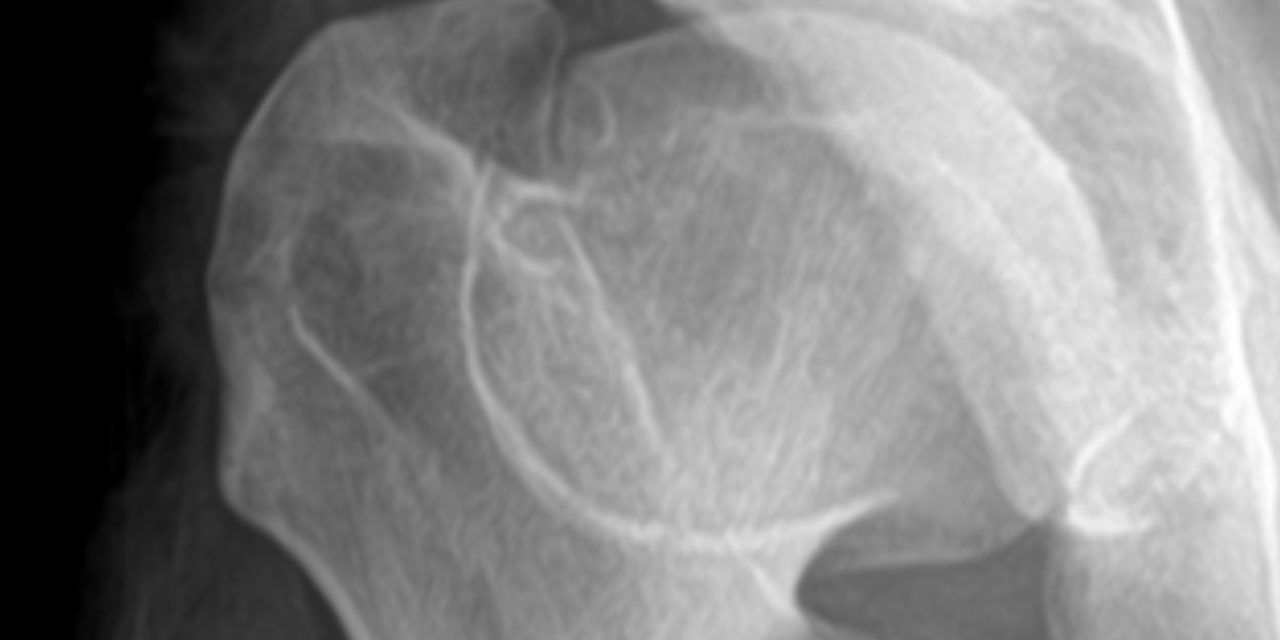

Radiographs of the left hip reveal widening and flattening of the femoral head (coxa plana), widening of the proximal femoral neck (coxa magna), and a thin curvilinear sclerotic line extending across of the femoral neck (“sagging rope sign”). These findings illustrate the classic appearance of the advanced healed stage (stage 4) of Legg-Calve-Perthes disease (LCPD). Note that the acetabulum is usually of normal contour without femoral head dislocation/ subluxation; this is an important differentiating factor when comparing LCPD to congenital dysplasia of the hip, in which acetabular flattening and femoral subluxation/ dislocation are typical findings.

There are several classifications systems used to classify the stages of LCPD; however, this paper will use the Waldentrom classification, which refers to the associated radiographic findings for each stage. The initial stage (stage 1) results from infarction, which produces a smaller and sclerotic epiphysis with medial joint space widening. This stage may be radiographically occult for 3-6 months. The fragmentation stage (stage 2) typically begins with a subchondral lucent line (crescent sign) and then progresses to fragmentation and resorption of bone, resulting in femoral head collapse and patchy sclerotic density. The re-ossification stage (stage 3) occurs as the ossific nucleus undergoes re-ossification in which the necrotic bone is resorbed and new bone replaces. The healing or remodeling stage (stage 4) consists of femoral head remodeling until skeletal maturity. Once fully healed, the remodeled hip has the classic coxa plana, coxa magna, and “sagging rope sign” radiographic features. Dependent upon proper treatment and other patient variables, the degree of resultant deformity will vary amongst patients.